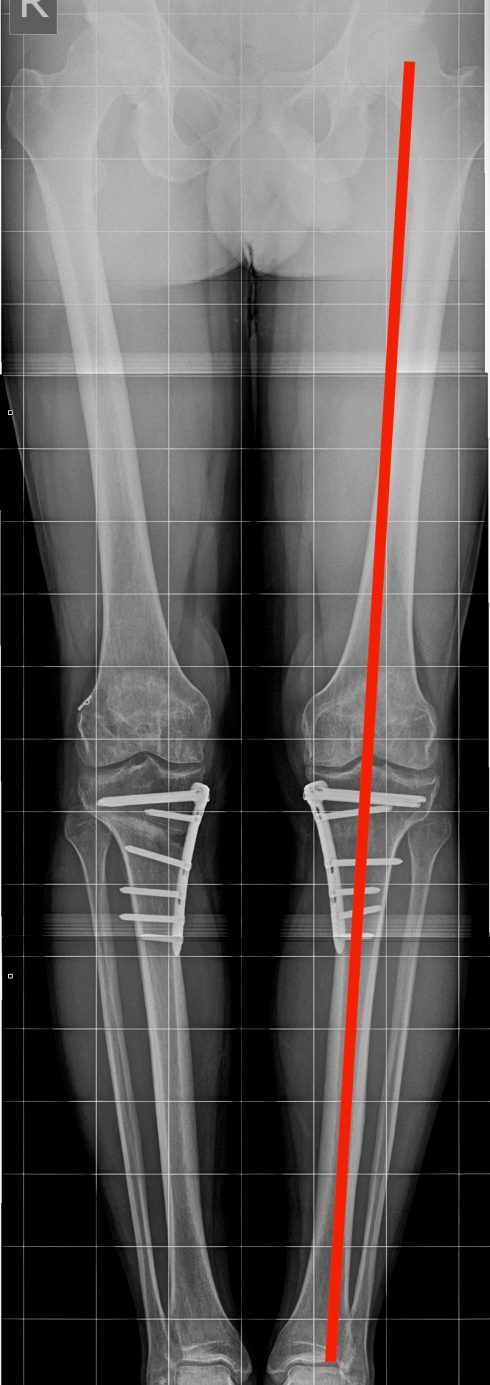

Przygotowując się do operacji, należy wykonać badanie rentgenowskie całych kończyn, by móc właściwe zaplanować osteotomię.

Osteotomia: przed (L) i po (P)